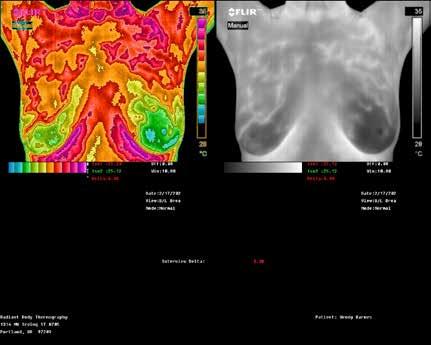

Upcoming Imaging Events